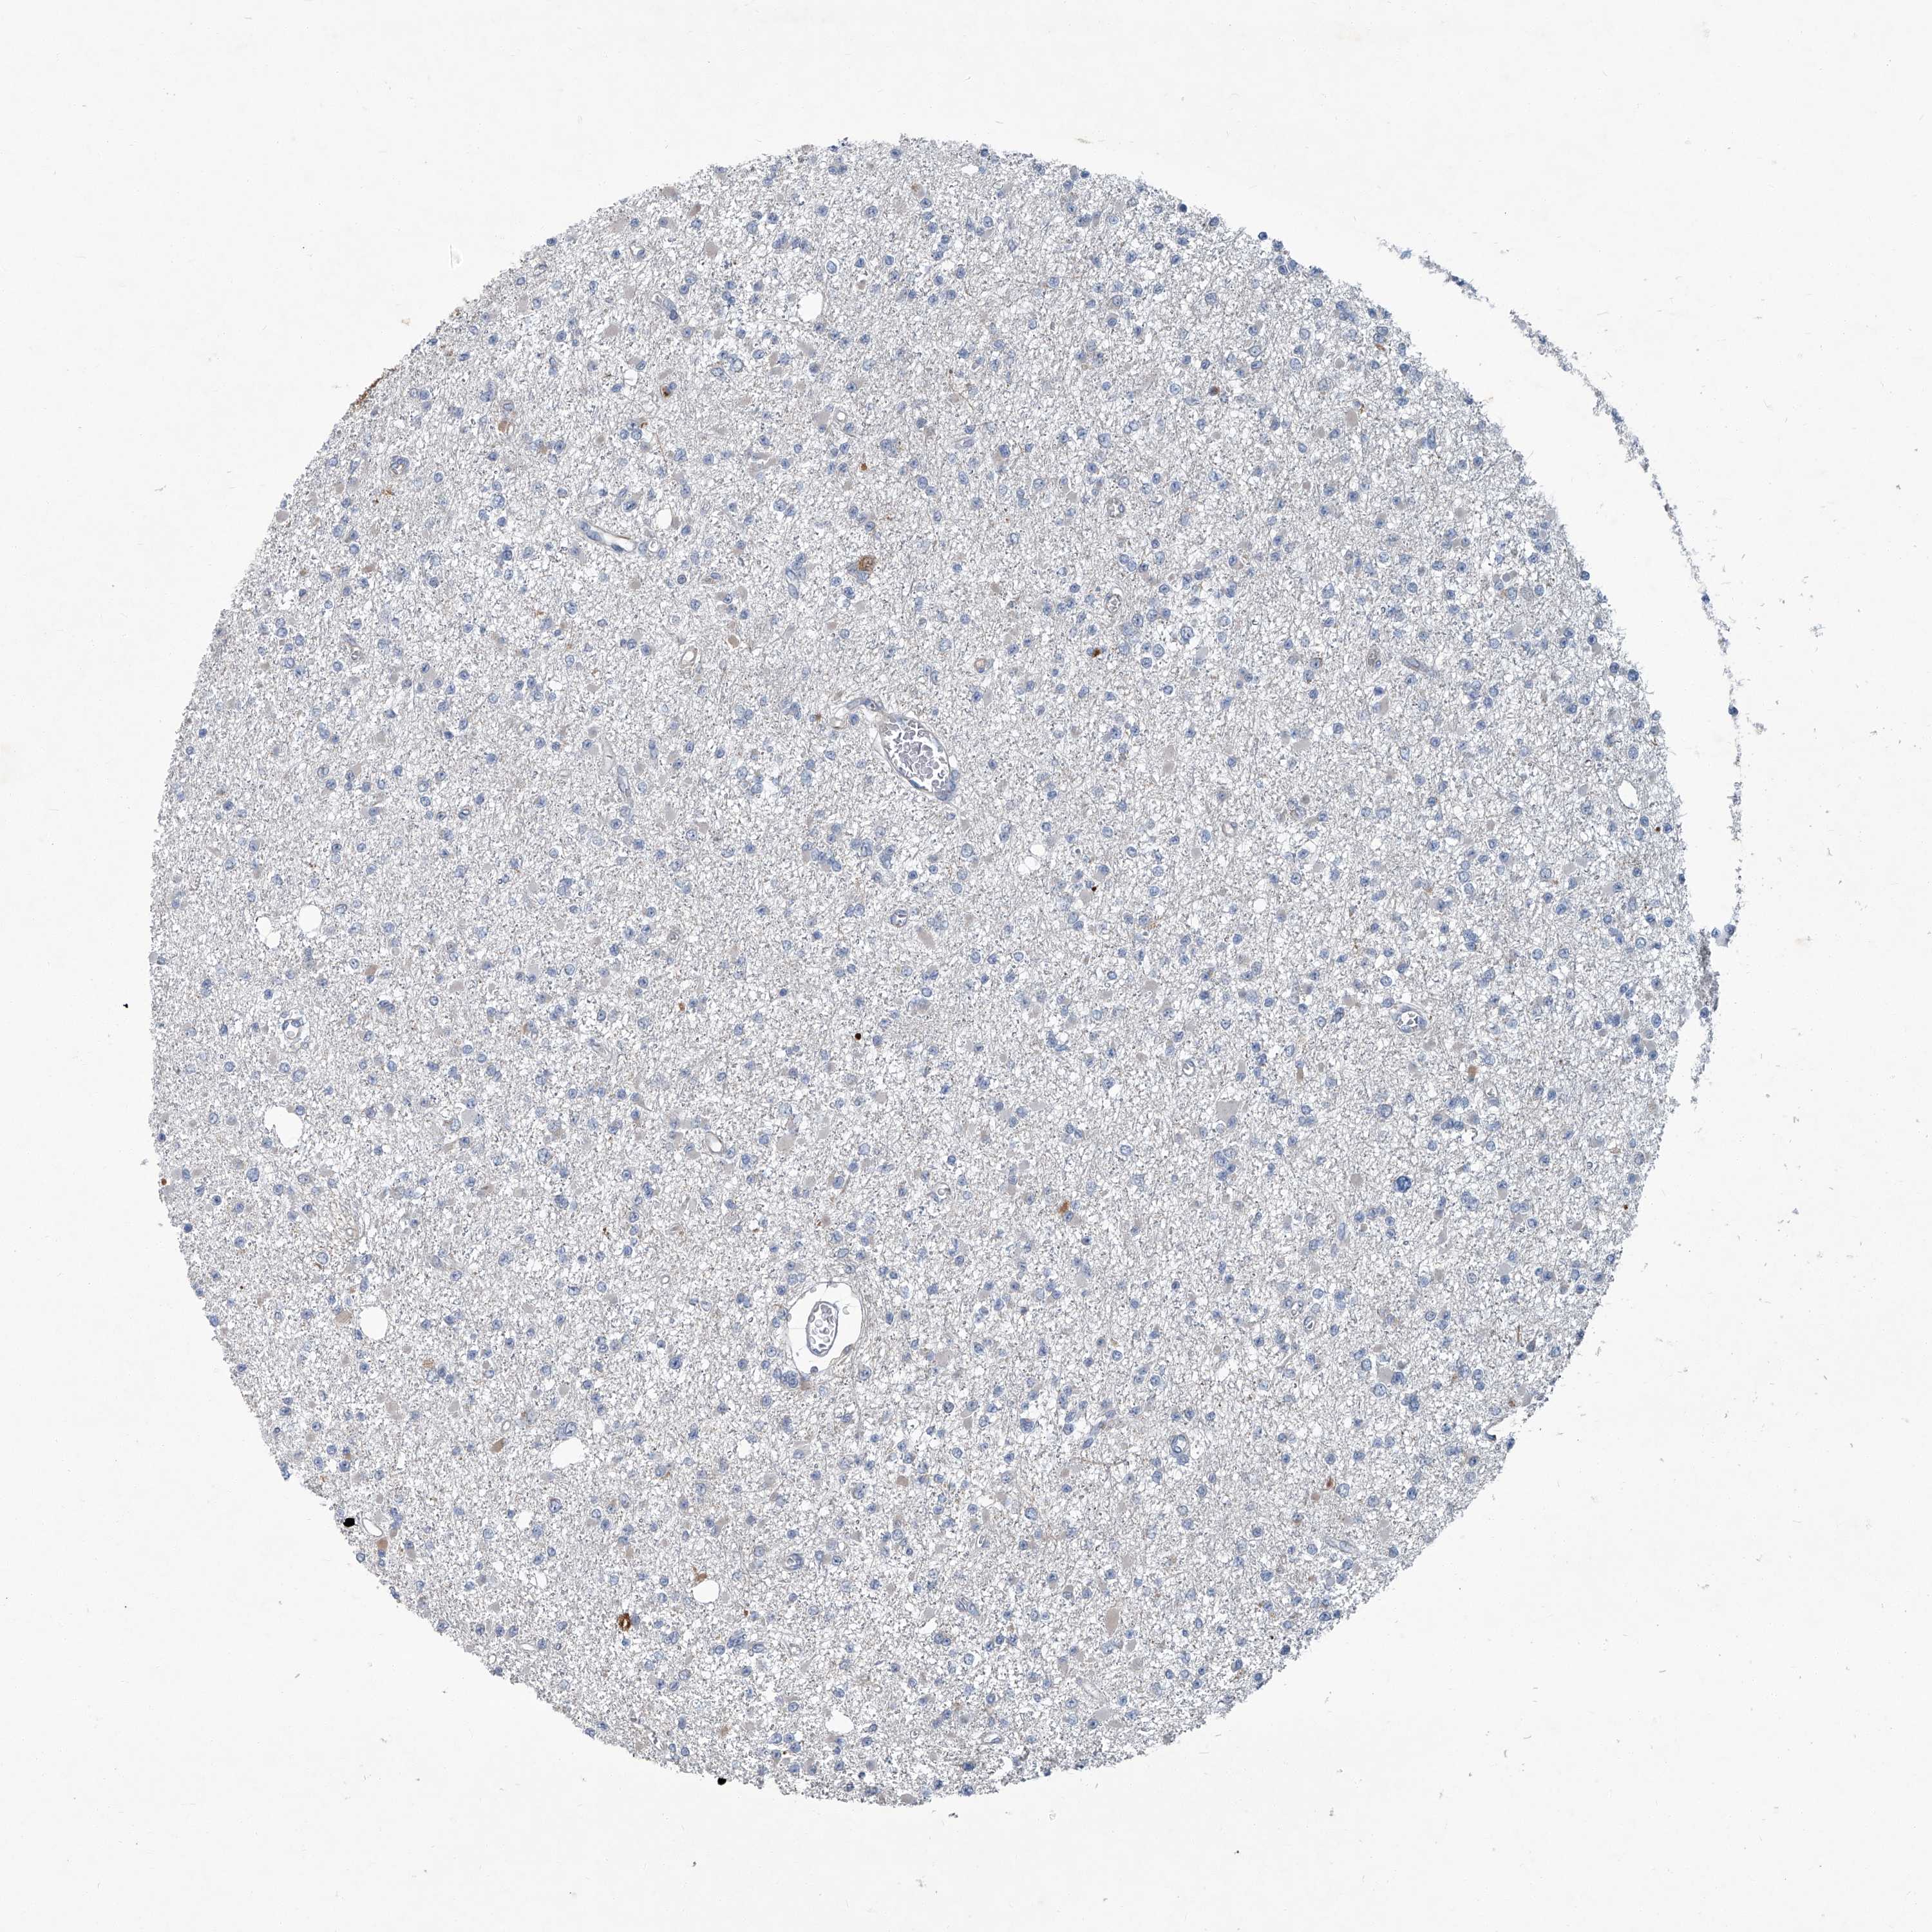

GLIOMA - Protein expressioni

A mouse-over function shows sample information and annotation data. Click on an image to view it in a full screen mode. Samples can be filtered based on level of antibody staining by selecting one or several of the following categories: high, medium, low and not detected. The assay and annotation is described here.

Note that samples used for immunohistochemistry by the Human Protein Atlas do not correspond to samples in the TCGA dataset.

Antibody stainingi

Antibody staining in the annotated cell types in the current human tissue is reported as not detected, low, medium, or high, based on conventional immunohistochemistry profiling in selected tissues. This score is based on the combination of the staining intensity and fraction of stained cells.

Each image is clickable and will lead to virtual microscopy that enables deeper exploration of all samples and also displays staining intensity scores, fraction scores and subcellular localization as well as patient and tissue information for each sample.

Antibody HPA030270

Antibody HPA030271

Antibody HPA030272

Staining

High

Medium

Low

Not detected

Intensity

Strong

Moderate

Weak

Negative

Quantity

>75%

75%-25%

<25%

None

Location

Nuclear

Cytoplasmic/membranous

Cytoplasmic/membranous,nuclear

Glioma, malignant, High grade

Glioma, malignant, Low grade

Glioblastoma, NOS